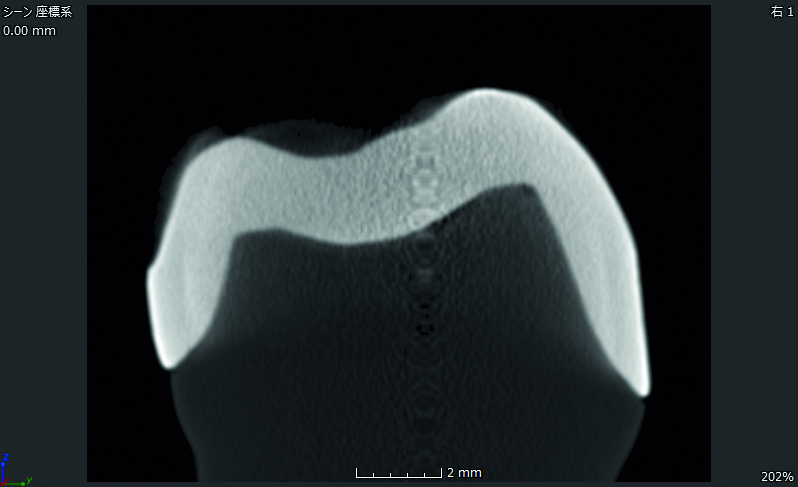

Limites plus précises

Étant entièrement cristallisé avant fraisage, Initial™ LiSi Block peut être fraisé directement avec des limites cervicales lisses et précises. Autrement, il peut être cuit après coloration et conserver une grande précision des limites cervicales.

Comparaison de Initial™ LiSi Block avec IPS e.max CAD en termes de limites cervicales :

GC LiSi block vs e.max cadInitial™ LiSi Block

GC LiSi block vs e.max cadIPS e.max CAD